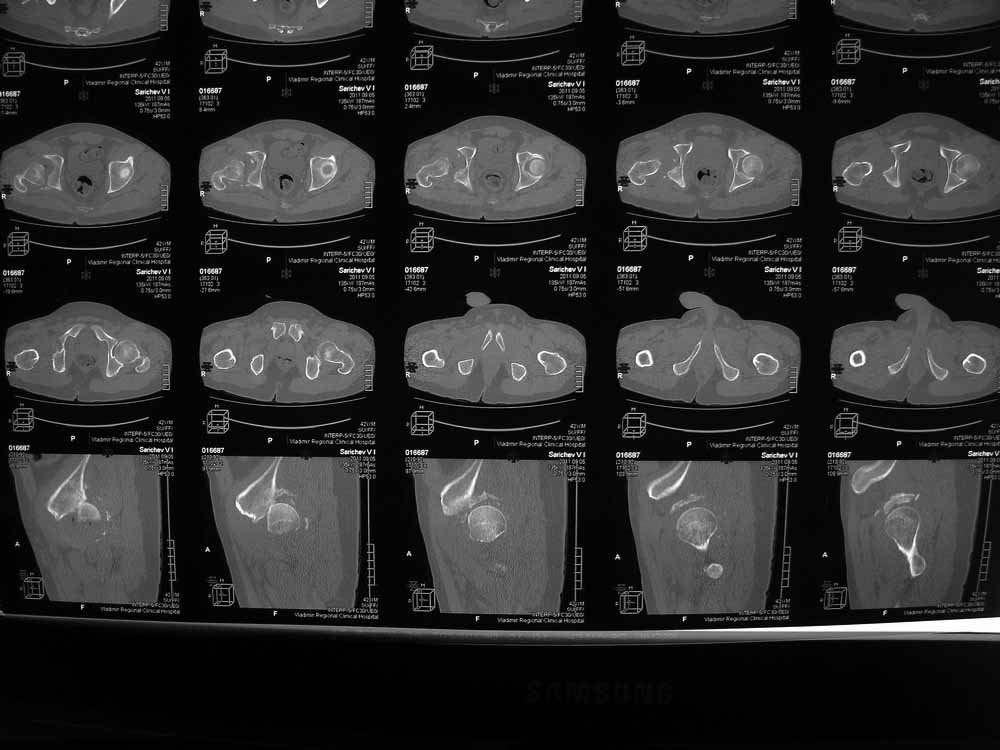

Вот еще сканы.

В этой ситуации предпочел бы эндопротез, шансы на жизнеспособность головки в таком сроке вывиха исчезающе малы, попытка синтезировать задний край в этих же сроках (ретракция мышц, рубцы) скорее всего приведут к его девитализации с последующим аваскулярным некрозом. Выбор вертлужного компонента проще планировать после 3D, скорее всего можно будет обойтись стандартными предложением, возможно, с котилопластикой.